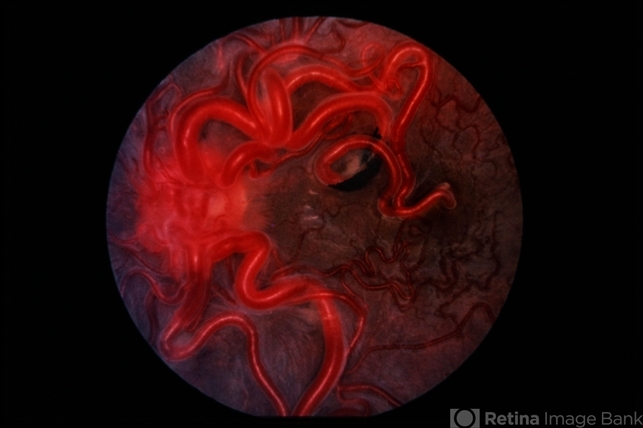

- WyburnMason Syndrome

- Wyburn-Mason, racemose hemangioma, arteriovenous malformation

- Racemose hemangiomatosis; Large arteriovenous malformation in the right eye.